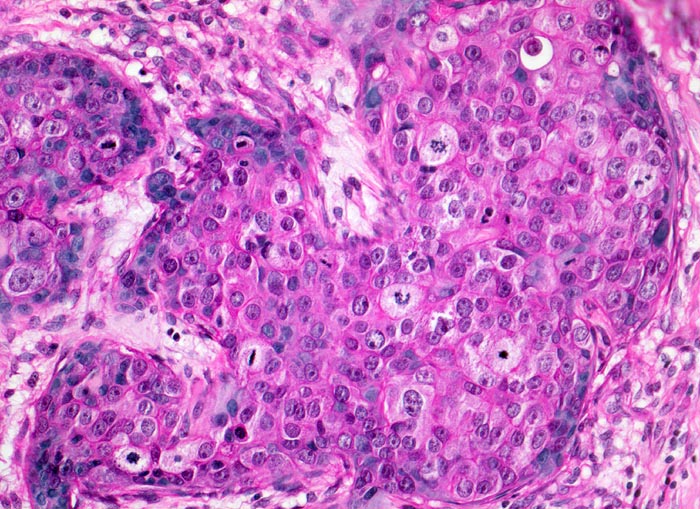

• Die Karzinomzellen sind deutlich grösser als die normalen sekretorischen Zellen der nicht neoplastischen Drüsenazini. Die vesikulären Zellkerne sind vergrössert, pleomorph und hyperchromatisch. Die Kernmembran ist teils irregulär. Die Tumorzellkerne enthalten prominente eosinophile Nukleolen.

• Das Zytoplasma einiger Tumorzellen enthält runde bis ovale hyaline Globuli, teils umgeben von einem Halo (unspezifischer Befund).

• Das Karzinom ist gering differenziert: B.R.E. Grad 3; Score 8: 3, 3, 2. Keine Drüsenbildung: Score 3 Starke Zellatypien: Score 3 <10 Mitosen/10 HPF: Score 2